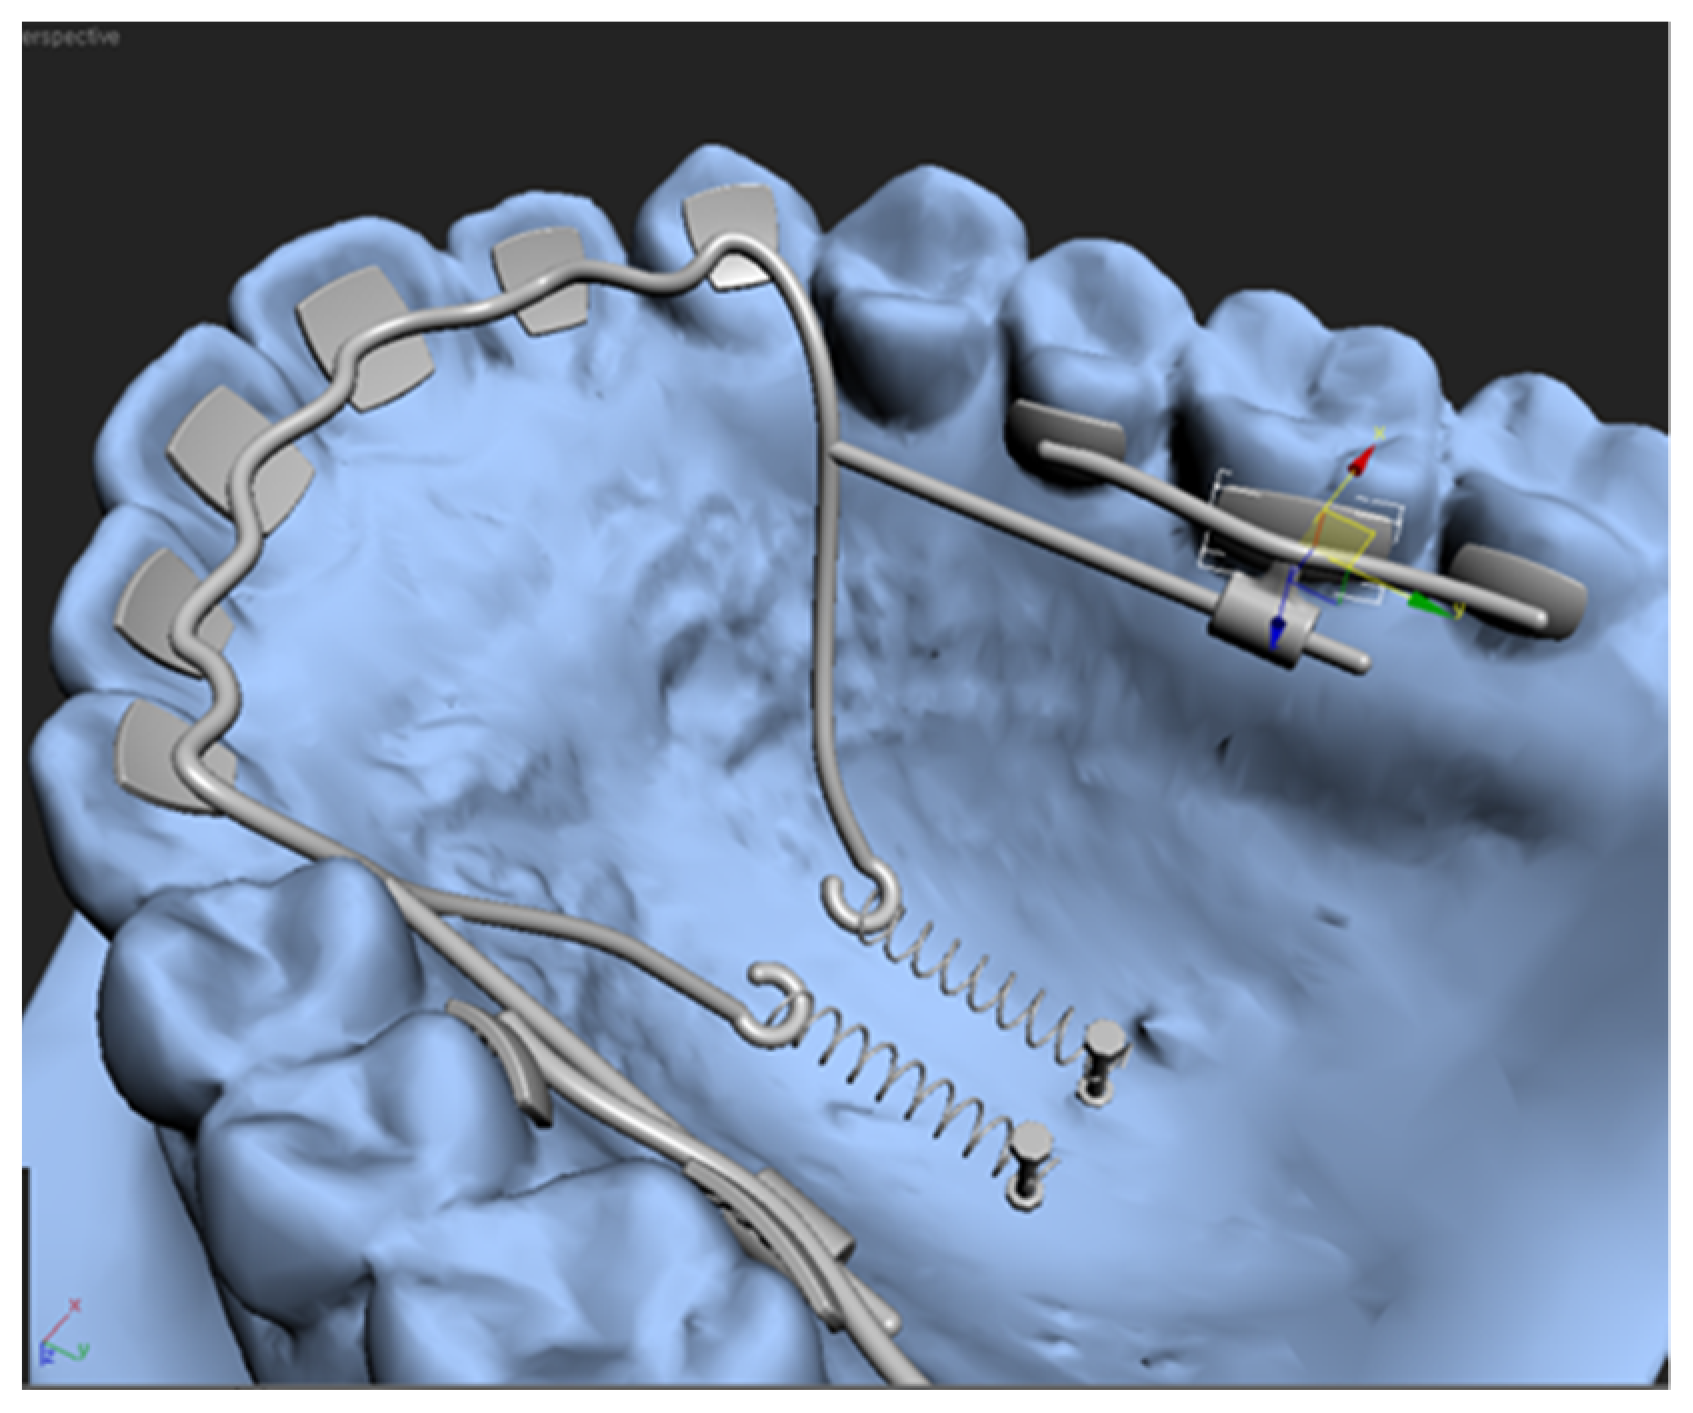

Kwon et al. showed that APLR (KILBON) can be designed using CAD/CAM soft-ware including 3Txer (ver. 2.5, Orapix, Seoul, Korea) and Rhinoceros 3D (ver 5.0, Rob-ert McNeel & Associates, Seattle, WA, USA) (Figure 12) [24]. Because 3D digital technology is rapidly developing, it is judged that these technologies will be applied to lingual retractors in various ways, and accordingly, lingual retractors are expected to become more popular.

Figure 12.

Virtual design of antero-posterior lingual retractor with software program.